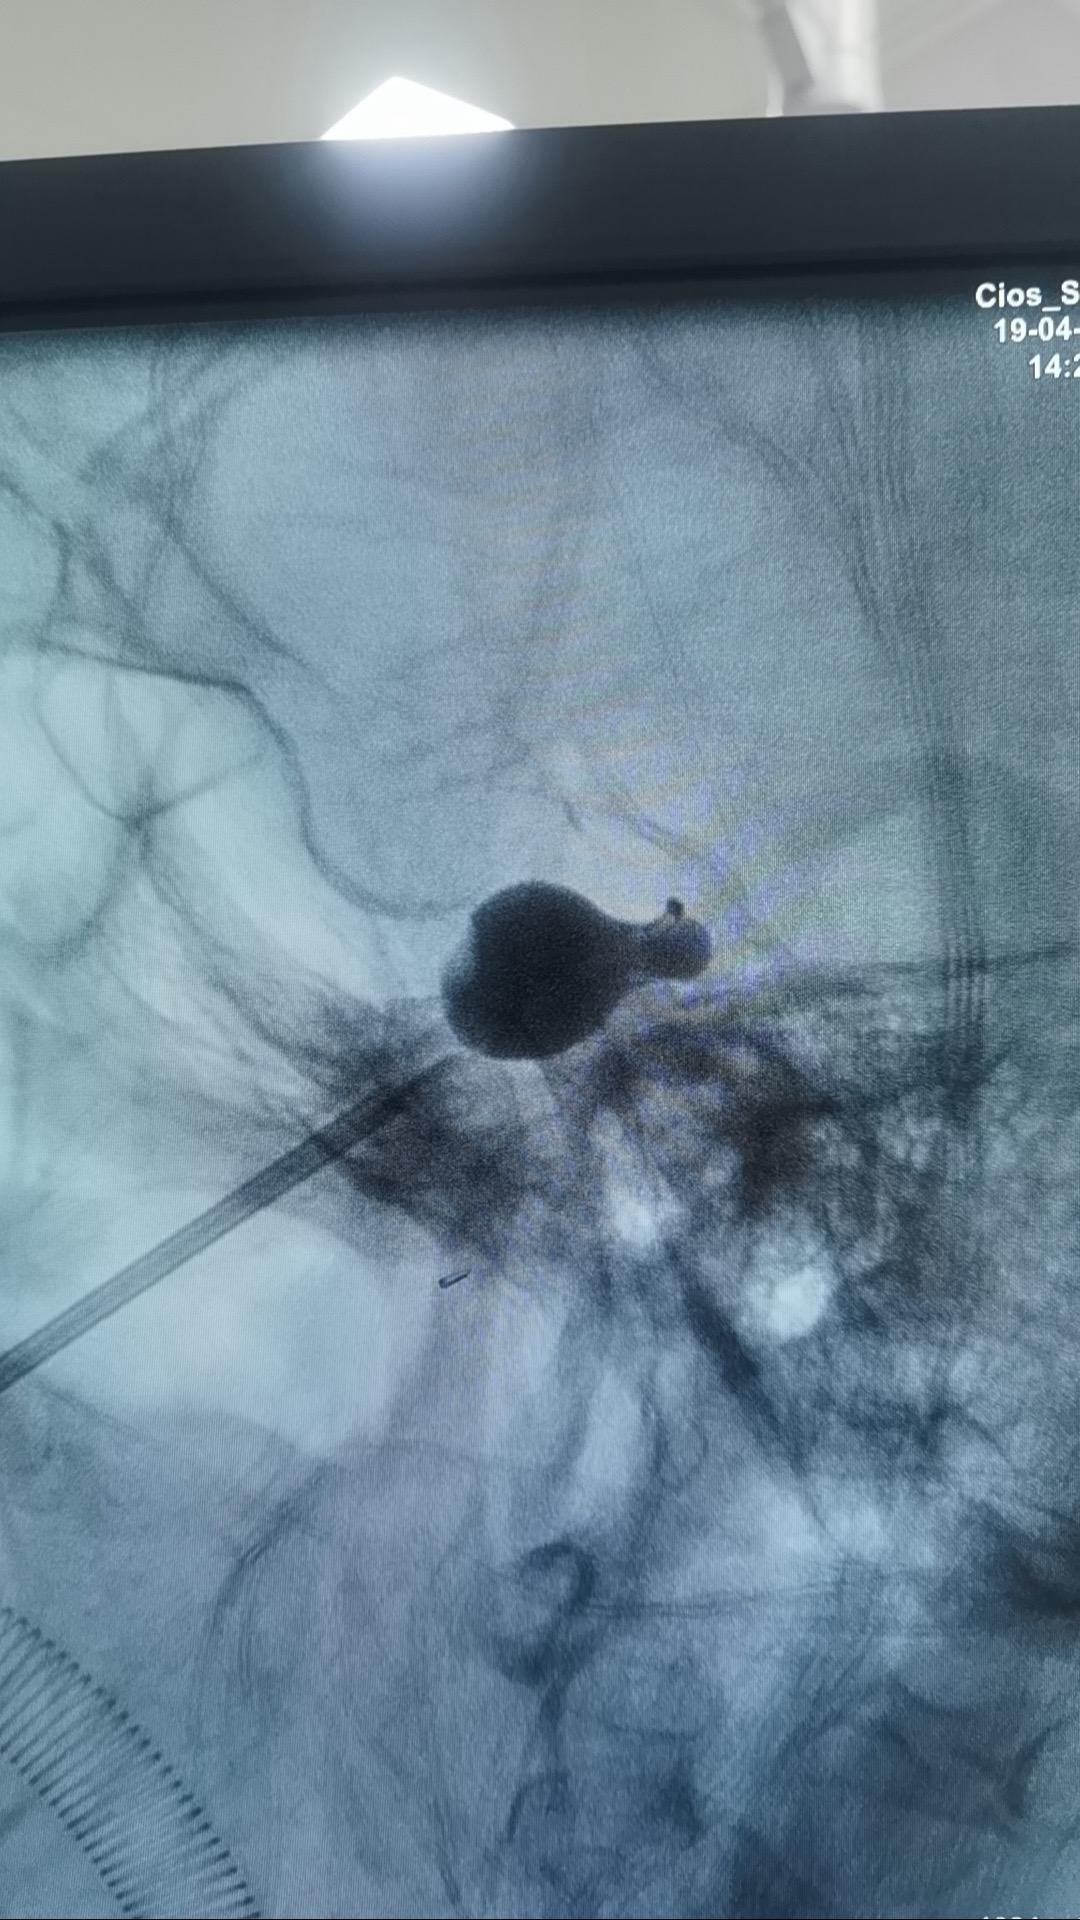

三台手术完成。今天紧凑了一点,一台脑起搏器植入治疗帕金森病,一台三叉神经痛减压,一台三叉神经痛球囊压迫术